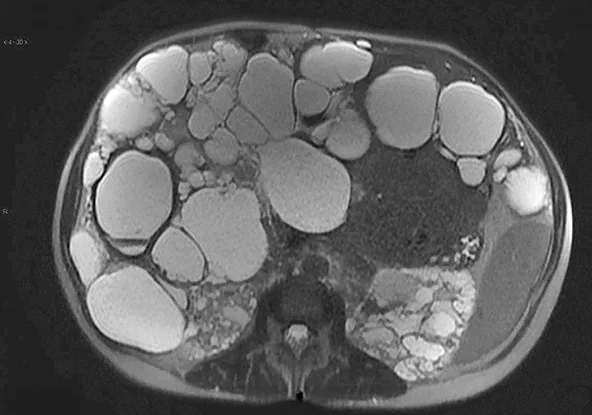

Figure 10 : Polykystose hépatique secondaire à une mutation de PKD1 visualisée sur une IRM hépatique en séquence pondérée T2

Le diagnostic est facilement porté par l’échographie hépatique qui montre de multiples kystes (> 10) supracentimétriques, au contenu anéchogène, avec renforcement postérieur. Ces kystes ne sont pas communicants avec les voies biliaires. En cas de polykystose hépatique non compliquée, le scanner ou l’IRM hépatique ne sont pas indiqués. L’IRM montre classiquement de volumineux kystes non communiquant, en hyposignal T1 et hypersignal T2 (figure 10). La présence de bulles d’air intra-kystiques permet de poser le diagnostic d’infection de kyste. L’hémorragie intra-kystique peut être diagnostiquée en échographie par la visualisation d’un sédiment intra-kystique et en IRM par la visualisation d’un contenu intra-kystique hétérogène en hypersignal T1 et T2 qui témoigne du saignement récent.